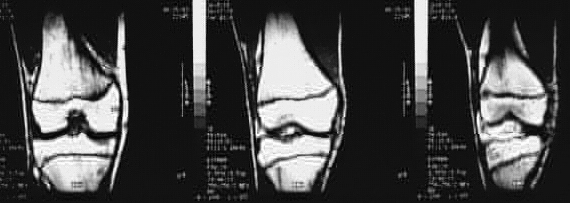

Radiology Images

Lower Limbs: Knee MRI Coronal 2 of 2